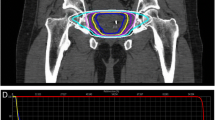

Approximately 2 weeks before treatment planning, 4 gold fiducial seeds were placed transperineally in each patient to allow for motion tracking during treatment. Two of the seeds were implanted at the prostate apex and two were implanted at its base. After allowing time for possible seed migration, treatment planning was performed prior to the treatment day using a CT scan (1.5-mm cuts) with MRI fusion. All pretreatment imaging was performed with the patient in the same position that was used for his treatment delivery. For low-risk patients, just the prostate made up the gross target volume (GTV). For intermediate- to high-risk patients who had a Gleason Score of greater than 6 and a PSA of greater than 15 ng/ml, the proximal half of the seminal vesicles was added to the GTV. After the GTV was delineated, a margin was added to create the planning target volume (PTV). For low- and intermediate-risk patients, the margin was extended 5 mm on all sides except for posteriorly (by the rectum) where a 3-mm margin was used. For high-risk patients, an 8-mm margin was added to the involved side. All patients had the bladder, prostate, rectum, seminal vesicles, and penile bulb contoured; the urethra was not identified.

SBRT was delivered at two dose levels. The first 50 patients (16%) received a total dose of 35 Gy in 5 fractions of 7 Gy each to cover at least 96% of the PTV. The subsequent 254 patients (84%) received a total dose of 36.25 Gy in 5 fractions of 7.25 Gy to cover at least 96% of the PTV. The dose was increased to 7.25 Gy per fraction when preliminary reports at scientific meetings indicated that the higher dose could be delivered safely (based on early results of the study by King et al. of Stanford University; [18]). The mean number of beams was 152 (range, 140–170). The mean D50 to the bladder and rectum was 43% and 41% of the prescribed dose, respectively.